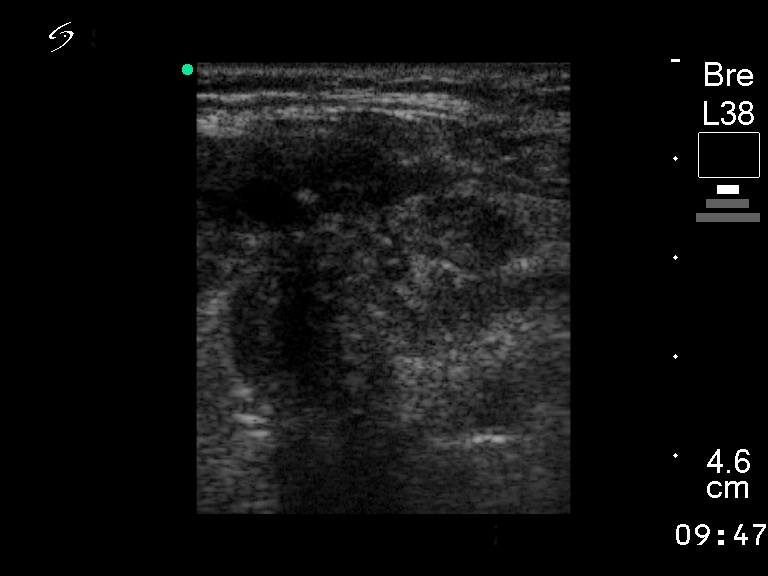

Ultrasonography. There was a large, hypoechogenic inhomogeneous nodule which occupied almost the entire right lobe and the isthmus. The left lobe was intact. There was a hypoechogenic inhomogeneous lesion within the right parotid.